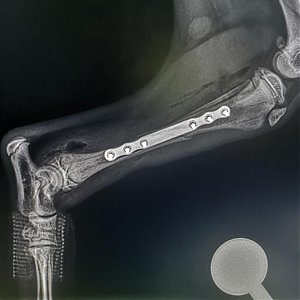

Šteniatko muselo podstúpiť zákrok, ktorým cieľom bolo zoperovať komplikovanú fraktúru. Musíme potvrdiť, že šteniatku sa viedlo veľmi dobre. Hneď na druhý deň po zákroku, mala Valentínka naozaj skvelú náladu. Vôbec nepôsobila tak, že podstúpila náročný zákrok.